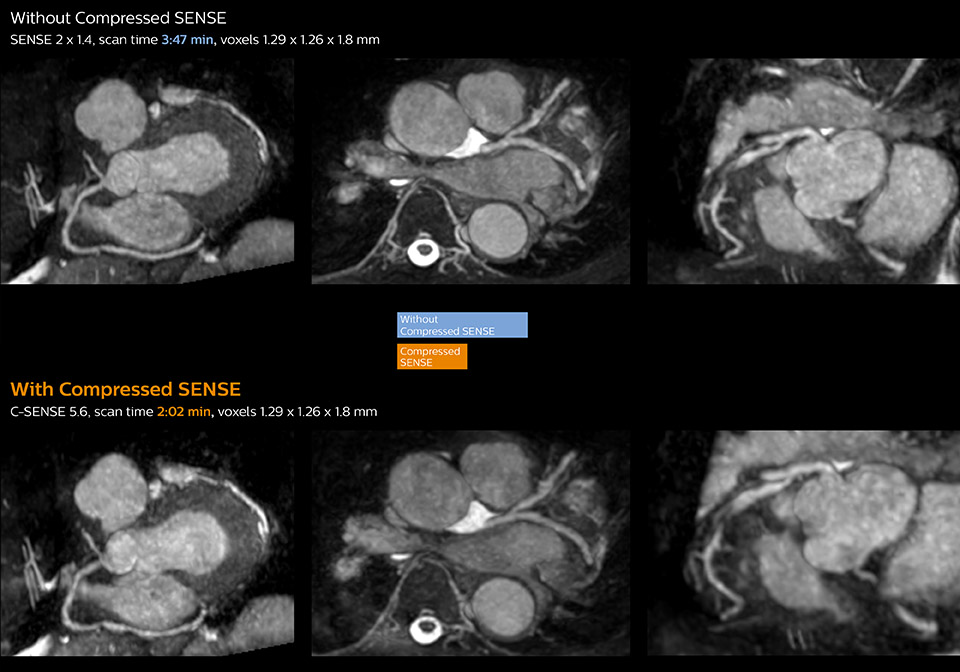

These images of a patient with acute myocardial infarction images were acquired on Ingenia 1.5T with and without Compressed SENSE.

These images with and without Compressed SENSE were acquired on Ingenia 1.5T.

“Compressed SENSE has now been implemented in all cardiac exams. Thanks to the acceleration, fewer breath holds are now needed, or breath hold times are shortened. This reduces the burden of the exam for cardiac patients, without affecting the quality of information required for cardiac function analyses,” he says. “Because it’s easier for patients to comply with the breath hold times” “In our previous cardiac cine sequence, we were acquiring two slices during one breath hold. With Compressed SENSE, we increased this to four slices per breath hold. It is also possible to shorten scanning time using a C-SENSE factor 6 without sacrificing image quality.”

“Typically, in scans with high contrast, such as 2D balanced TFE cine, a quite high C-SENSE factor may be used. When we tried a higher C-SENSE factor, we saw still no significant influence on cardiac ejection fraction, but 2D image quality started to decline. For coronary imaging, we use a C-SENSE factor of 3 in 3D balanced TFE, or even up to 4 when contrast is high.”